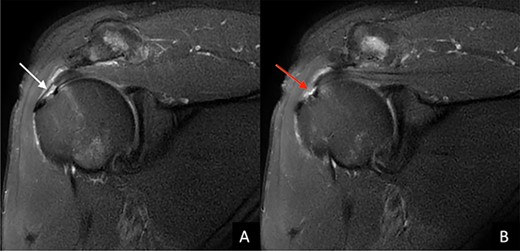

Magnetic resonance imaging (MRI) demonstrated a full-thickness tear of the distal supraspinatus tendon and a partial-thickness articular sided tear of the infraspinatus tendon (Fig. 2).

T2-weighted coronal MRI image of the left shoulder shows (A) the degree of medial to lateral involvement (white arrow) of (B) the full thickness tear of the distal portion of the supraspinatus tendon.